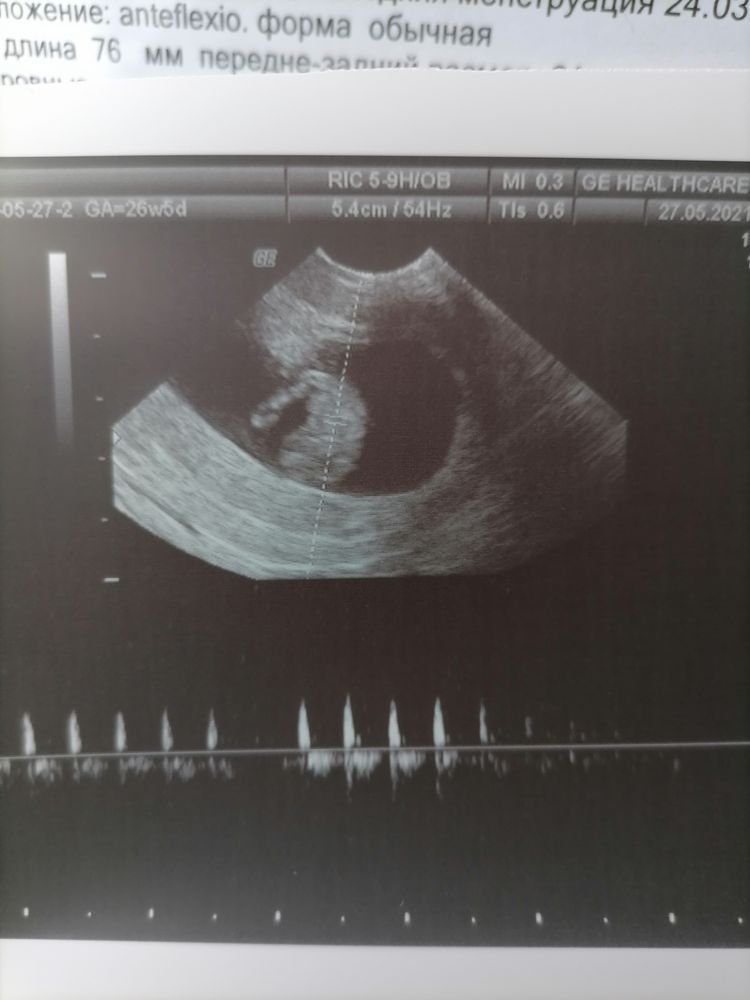

Все в порядке с моей фасолинкой🥰

Первое УЗИ! Срок 5,3🤰 Чат Январята